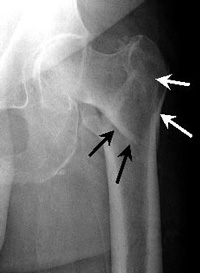

This fracture occurs between the neck of the femur and a lower bony prominence called the lesser trochanter. The lesser trochanter is an attachment point for one of the major muscles of the hip. Intertrochanteric fractures generally cross in the area between the lesser trochanter and the greater trochanter. The greater trochanter is the bump you can feel under the skin on the outside of the hip. It acts as another muscle attachment point.

Hip fractures occur at the upper end of the thigh bone (femur).

Intertrochanteric Fracture. This occurs further down the bone and tends to have better blood supply to the fracture pieces.

Stable Impacted Fracture. Certain fractures that have not moved ("displaced") may not require surgery. Because there is a risk that they may move later on, they are often fixed.